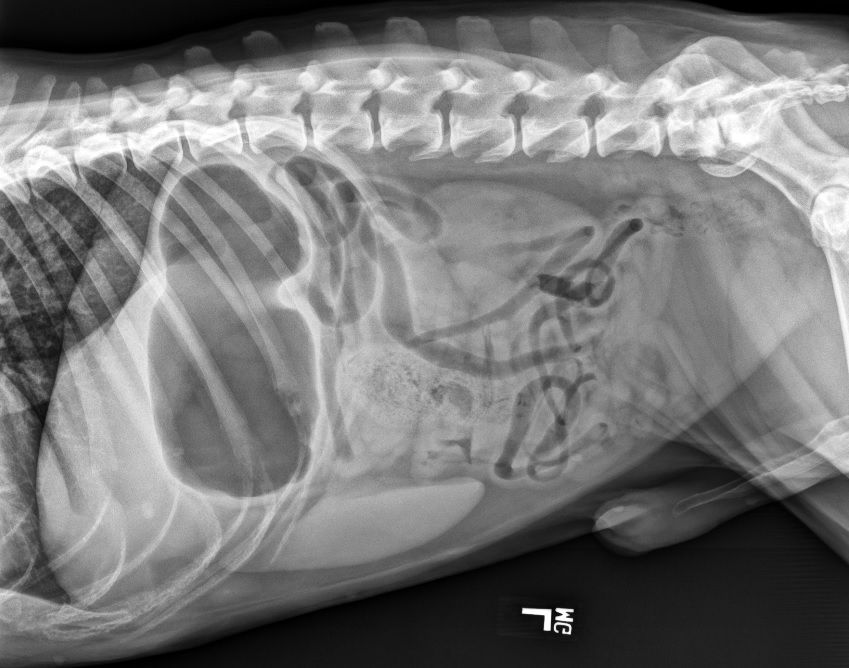

Initial diagnostics in a vomiting animal should include abdominal imaging. Three-view abdominal radiographs and ultrasound are the most common forms of imaging.

When evaluating abdominal radiographs, 2 populations of bowel are characteristic for a mechanical obstruction. Historically, in dogs, a ratio greater than 1.6 comparing the diameter of small intestine to the height of L5 vertebra has been recommended to determine presence of obstruction.1 In cats, this has been reported as a ratio greater than 3.0 when comparing the diameter of small intestine to height of the cranial end plate of L2 vertebra.2 However, more recent findings in literature have shown that objective ratios don’t provide more accuracy than subjective evaluation.3